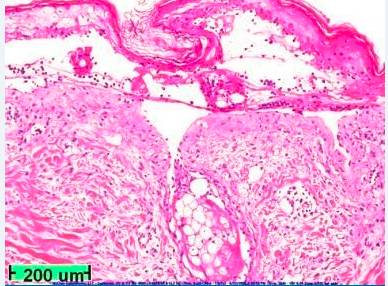

患者住院接受治疗,查血常规及尿常规,发现其轻度贫血,非特异性白细胞轻微增多,白细胞介素-6(IL-6)和C反应蛋白(CRP)水平升高。电解质和其他化学物质正常。皮肤科医生会诊后进行皮肤活组织检查,结果显示表皮全层坏死,皮肤炎症细胞轻度浸润(图2)。

图2